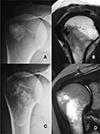

Of the 19 Type III cases with bone involvement, twelve were classified as Type III-a (cortical erosion without intraosseous extension) (Figure 3), six as Type III-b (intraosseous extension through a cortical breach) (Figure 4), and one as Type III-c (deep medullary involvement) (Figure 5). The “hourglass sign”, indicating continuity between the tendon deposit and intraosseous component, was observed in 83% of Type III-b cases (Figure 4C).

Figure 5 A. AP view showing a calcification located in the tendon of the infraspinatus muscle. B. Oblique sagittal MRI view showing the calcification and the intraosseous deposit. C. Anteroposterior (AP) radiographic image showing extension to the medullary canal of the humerus D. MRI coronal view highlights intramedullary extension. |

Type III involvement occurred in 18% of supraspinatus cases, 15% of infraspinatus cases, and 33% of subscapularis cases. Notably, the only teres minor case presented with central intraosseous extension (Type III-c) (Table 1; Figures 1F and 5). The infraspinatus location showed a stronger association with intraosseous subtypes.